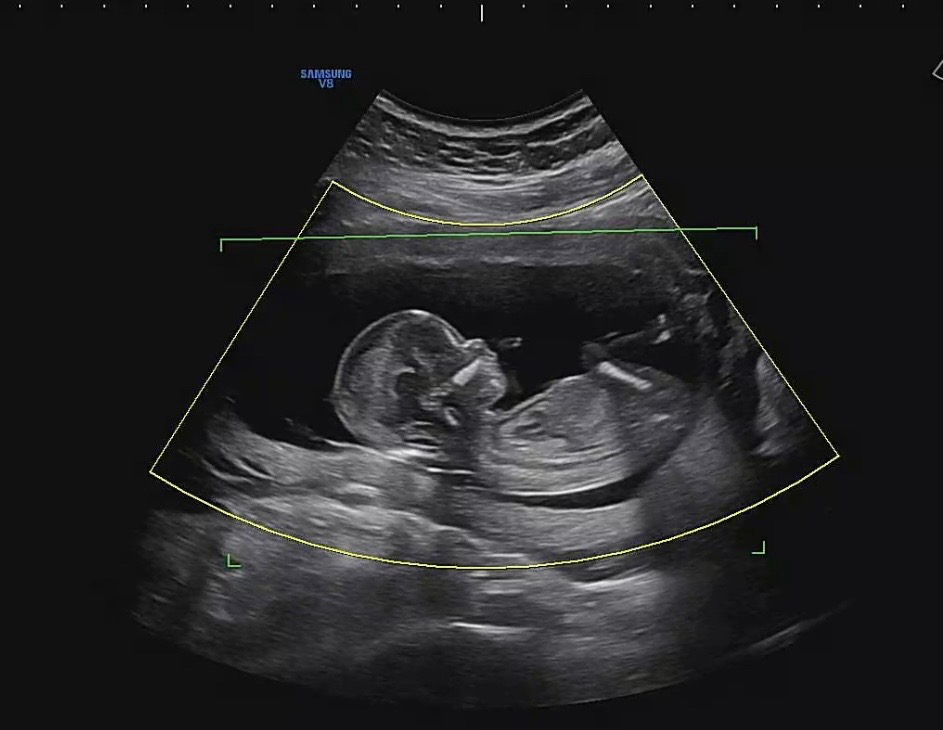

13주차 각도법 봐주세요

첫째가 아들이라서 둘째 성별이 너어무 궁금해요 태몽도 딸이라 저도 살짝 기대중이라 😅 투표해주세요